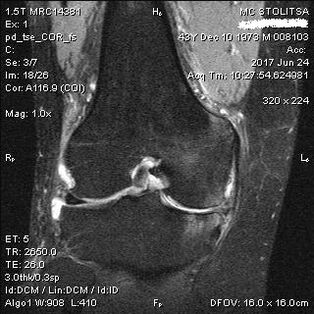

Diagnosis arthrosis sendi lutut dilakukan di kantor ahli reumatologi atau ahli ortopedi. Dokter memeriksa sendi yang terkena, merabanya, mendengarkan keluhan dan mengajukan pertanyaan tambahan. Melakukan beberapa tes - misalnya meminta pasien menekuk kaki atau berjalan beberapa langkah. Kemudian, jika perlu untuk memperjelas stadium penyakit atau sifat perubahan patologis, ia akan merujuk Anda untuk penelitian tambahan. Misalnya untuk computer tomography atau radiografi.